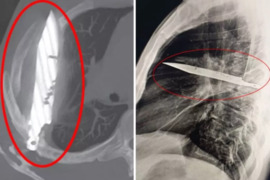

Ağrı ilə xəstəxanaya getdi, sinəsində 8 ildir bıçaqla yaşadığı ortaya çıxdı

Tanzanyada 44 yaşlı kişi, sağ döşünün altından irin axması şikayəti ilə xəstəxanaya müraciət edib. türk mediasına istinadən xəbər verir ki, həkimlər ilkin müayinədə ağrı, nəfəs darlığı, öskürək və ya hərarət kimi əlamətlər aşkar etməsə də, rentgen nəticəsi hər kəsi təəccübləndirib – kişinin döşündə ta